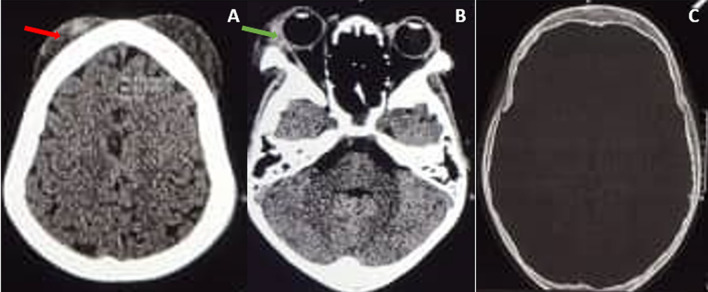

Case presentation: A 9-year-old Ugandan male patient known to have sickle cell anemia presented to our pediatric emergency unit with areas of swelling of the head that progressed in a couple of hours to involve the right eye and were associated with a low-grade fever but no headache. A diagnosis of acute soft head syndrome complicated by orbital compression syndrome was made. The patient was treated conservatively with fluids, analgesia, steroids and prophylactic antibiotics. The orbital compression syndrome was complicated by a corneal ulcer; however, vision was retained in all visual fields due to the corneal ulcer's location below the pupillary axis.